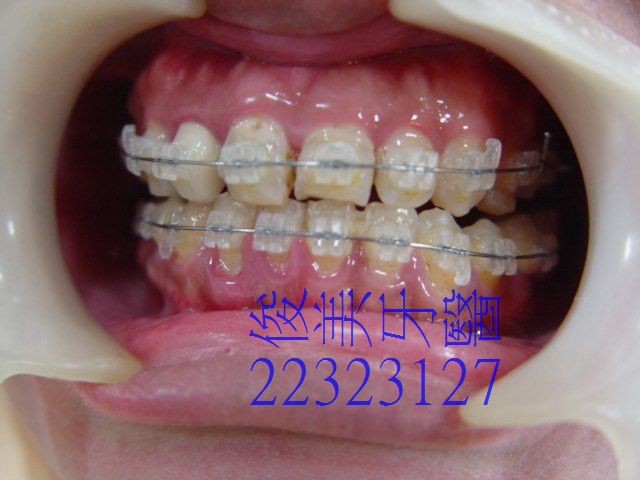

患者担心需拔牙才能做矯正,醫師評估:不需要再拔除小臼齒就可以將戽斗狀況改善。

患者很開心。

治療中,已改善戽斗狀況,不再是反咬的狀況了。